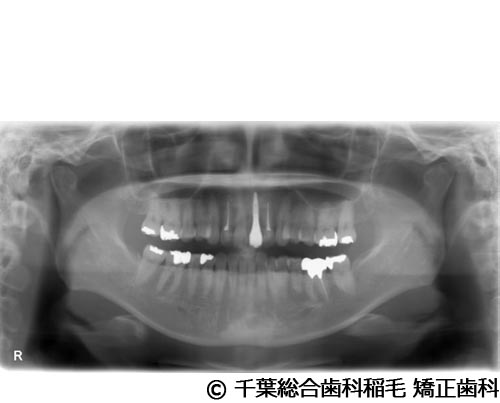

【症例4】上顎前歯1本インプラント埋入手術

- 治療前

- 治療後

- 治療名

- 上顎前歯1本インプラント埋入手術

- 費用

- 600,000円(税込)

- 期間

- 11ヵ月

治療内容

患者様の症状

前歯の色味が気になりご来院されました。

治療法

根っこが割れていたため抜歯となりました。

インプラント、ブリッジ、義歯それぞれのメリット、デメリットをお話させていただき、インプラントでの治療を選択されました。 -

治療結果

機能性、審美性ともに改善し、満足していただけました。

現在も定期検診で拝見させていただいています。